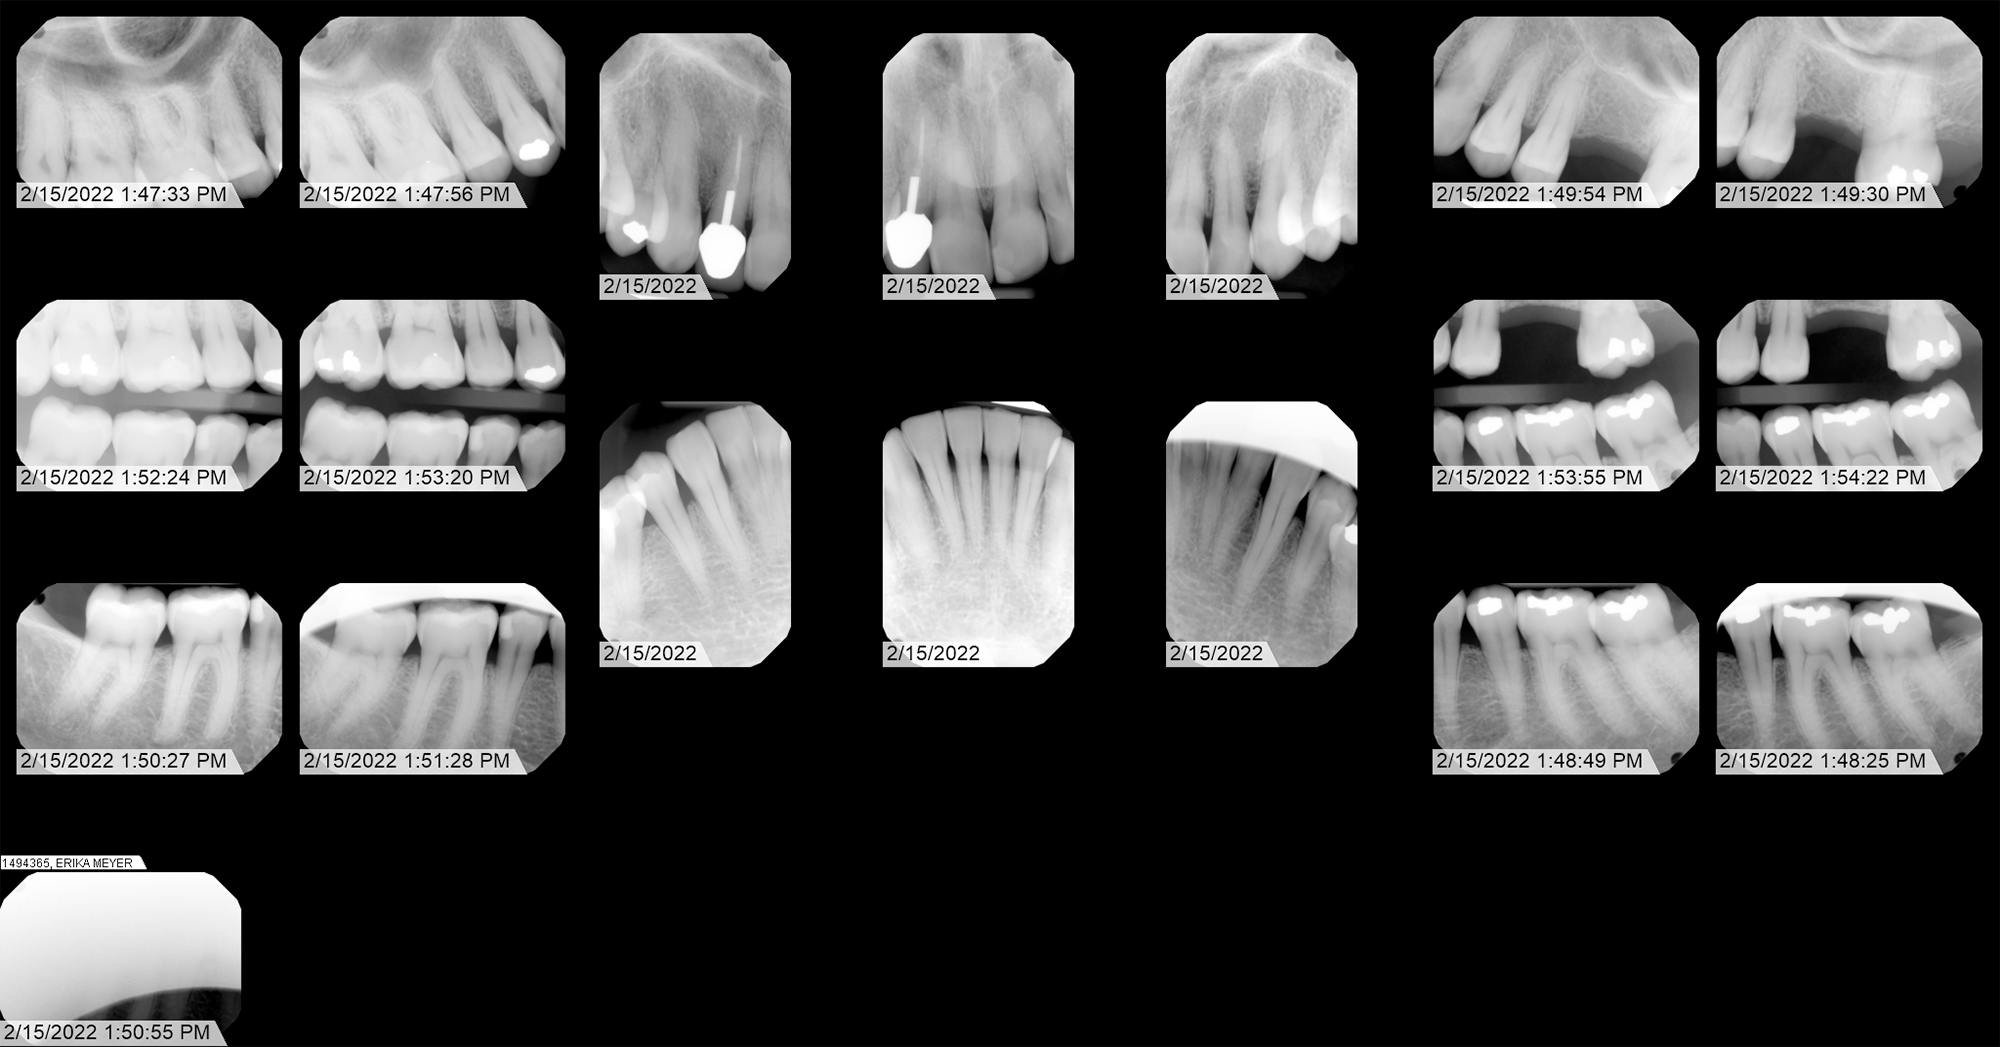

Radiographic Analysis (X-Ray)

Forensic identification of anomalous shape in extraction cavity.

Primary Exhibit

Case Narrative: Tooth 14

This featured x-ray, in my opinion, clearly shows an anomalous artifact embedded in my jawbone. This would have had to have been placed into the extraction cavity after the extraction and prior to suture. Dr. Patel is the only one who could have inserted this object - which appears to be a bioelectronic transceiver - into my jaw. Over time, the cavity fills with bone tissue, so the implant is now embedded in the jawbone.

Dental map showing numbered teeth. Tooth 14 extracted Jan 10, 2020